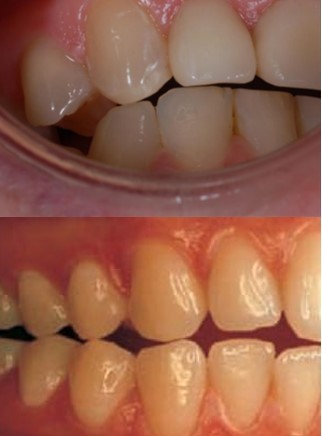

appaerance for pontic design

anteriorly - as ‘tooth like’ as possible

posteriorly - may compromise